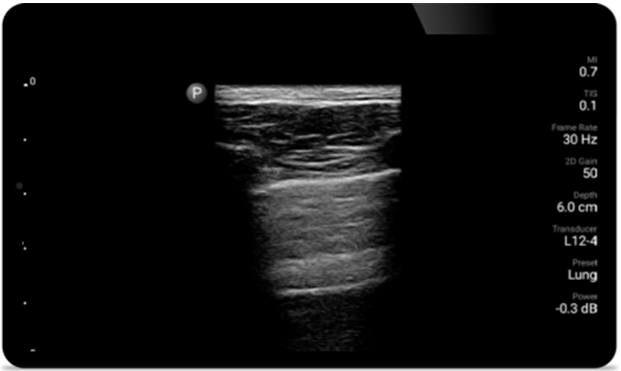

Aufatmen mit Lumify

Lumify kann helfen, Patienten schneller zu beurteilen und die Diagnosegenauigkeit häufiger Ursachen von Dyspnoe und anderen Lungenerkrankungen zu erhöhen.